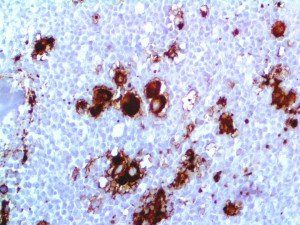

Clinical and laboratory manifestations of HLH include fever, enlarged liver and/or spleen, neurologic dysfunction, coagulopathy, liver dysfunction, cytopenias (i.e., low levels of erythrocytes, leukocytes, and/or platelets), hypertriglyceridemia, hyperferritinemia, hemophagocytosis, and eventually diminished NK cell activity as the immune system becomes progressively paralyzed. HLH can be familial (primary HLH) or secondary to another disease process (sHLH), such as rheumatic disease, in which it is referred to as macrophage activation syndrome (MAS, characterized by elevated ferritin).